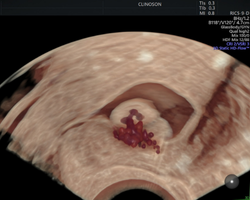

Apaixonado por diagnósticos precisos e tratamentos minimamente invasivos, sou especialista em exames avançados, como a avaliação da endometriose e o HyCoSy (Histerossonografia com Contraste), e também em tratamentos minimamente invasivos de miomas uterinos.

- Especialista em tratamentos de miomas uterinos

- Pioneiro na realização de ablação por Radiofrequência para miomas uterinos no Rio Grande do Sul e em Santa Catarina